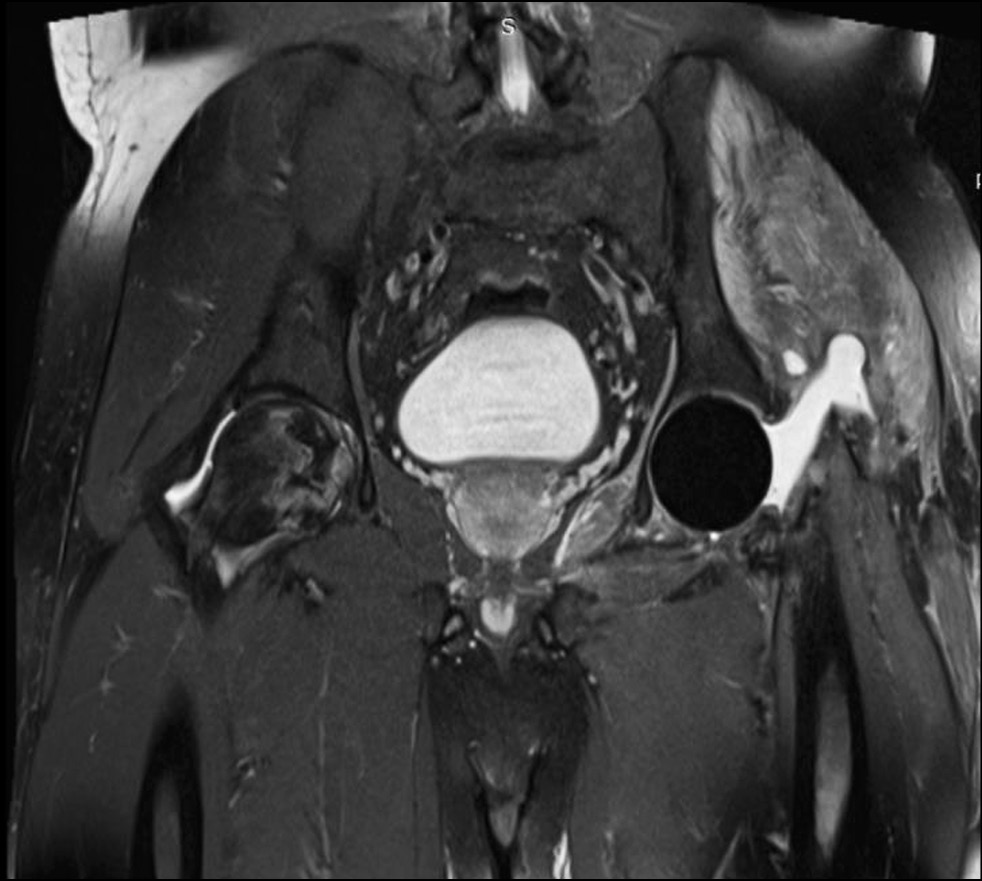

При выписке пациенту назначена амбулаторная схема пероральной антибактериальной терапии: ципрофлоксацин 750 мг 2 раза в день, рифампицин 450 мг 2 раза в день в течение 6 недель. На амбулаторном этапе пациент стал отмечать снижение болевого синдрома, передвигался с помощью костылей, эпизодов повышения температуры тела не наблюдалось. В динамике — стойкое снижение лабораторных маркеров системного воспаления: через 3 недели после операции СРБ — 15,4 мг/л, фибриноген — 3,53 г/л, СОЭ — 23 мм/ч. Через 6 недель после операции СРБ — 13,2 мг/л, фибриноген — 2,8 г/л, СОЭ — 18 мм/ч. Через 9 недель после операции СРБ — 8,0 мг/л, фибриноген — 2,8 г/л, СОЭ — 13 мм/ч. Оценка по шкале Harris Hip Score — 36 баллов, по ВАШ — 4–5 баллов. Оценка указанных клинико-лабораторных данных позволила предположить купирование воспалительного процесса. Для подтверждения этого амбулаторно была выполнена пункция тазобедренного сустава под рентгеноскопическим контролем для лабораторной оценки синовиальной жидкости. Экспресс-тест на лейкоцитарную эстеразу отрицательный, микробиологический анализ синовиальной жидкости — без роста. На контрольной МРТ тазобедренного сустава признаки артрита также отсутствовали (рис. 4).

Рис. 4. Послеоперационная магнитно-резонансная томограмма тазобедренных суставов пациента С., 38 лет, в коронарной проекции.

Учитывая положительную динамику, купирование воспалительного процесса, нормализацию лабораторных показателей, пациенту в плановом порядке проведён второй этап оперативного лечения — тотальное эндопротезирование тазобедренного сустава.